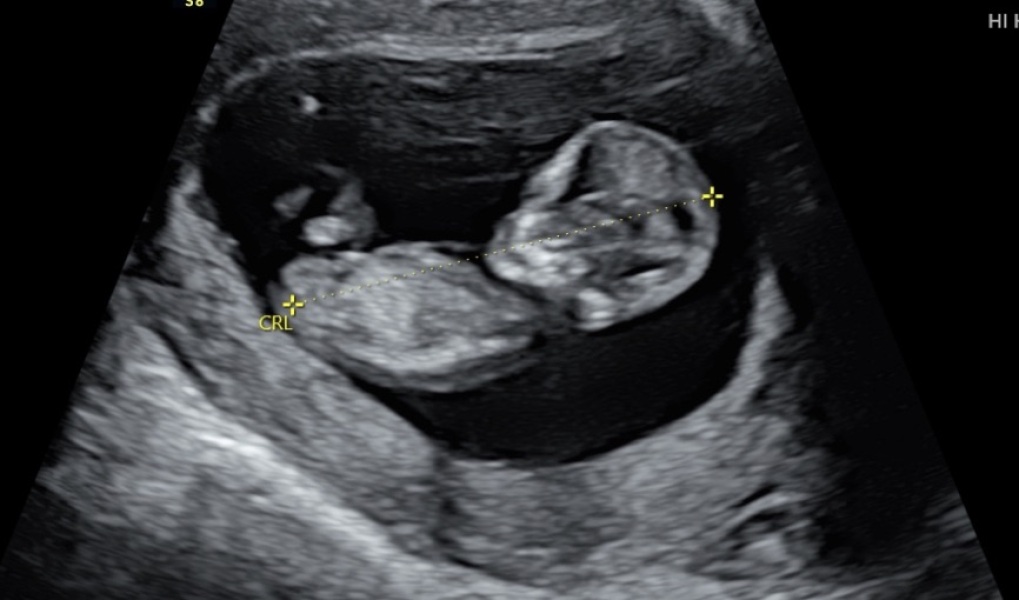

Nub theory, head shape, position... what do you think?!

12 week scan